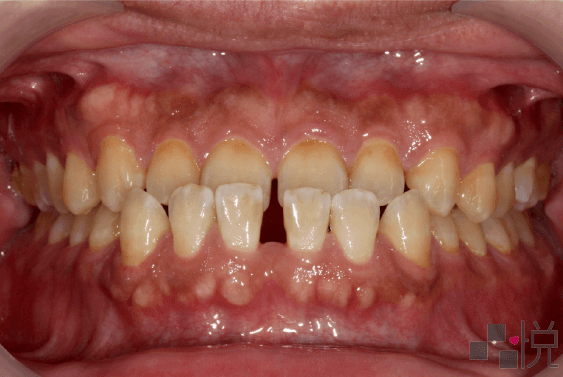

本案例矯正前是「假性戽斗」,齒列擁擠、深咬,還合併有前牙及後牙錯咬。

選擇不開刀(正顎手術)只做牙齒矯正,拔除狀況不好的上顎右側犬齒,以上顎第一小臼齒取代上顎犬齒。

矯正治療後齒列整齊,恢復正常咬合(上排牙齒蓋在下排外側),明顯改善深咬的情形,同時也改善戽斗的臉部外觀。